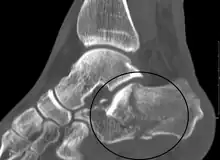

| X-ray of a fractured calcaneus | |

The Angle of Gissane, or "Critical Angle", is the angle formed by the downward and upward slopes of the calcaneal superior surface. On a lateral radiograph, an angle of Gissane > 130° suggests fracture of the posterior subtalar joint surface. Böhler's angle, or the "Tuber Angle", is another normal anatomic landmark seen in lateral radiographs. It is formed by the intersection of 1) a line from the highest point of the posterior articular facet to the highest point of the posterior tuberosity, and 2) a line from the former to the highest point on the anterior articular facet. Böhler's angle is normally 25° to 40°.[14] It is named after Austrian physician Lorenz Böhler.[16] A decreased angle is indicative of a calcaneal fracture.